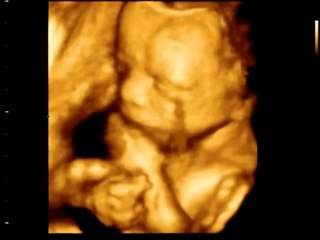

Беременность 11 недель(11 неделя беременности).mp4